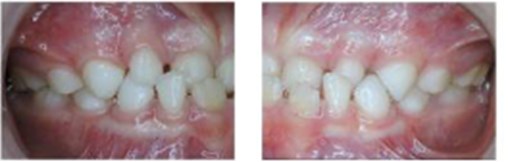

Figure 4 From Management Of Anterior Crossbite In Mixed Dentition Using

www.semanticscholar.org

www.semanticscholar.org

Figure 4 From Management Of Anterior Crossbite In Mixed Dentition Using

www.semanticscholar.org

www.semanticscholar.org

Figure 4 From Management Of Anterior Crossbite In Mixed Dentition Using

www.semanticscholar.org

www.semanticscholar.org

Figure 4 From Management Of Anterior Crossbite In Mixed Dentition Using

www.semanticscholar.org

www.semanticscholar.org